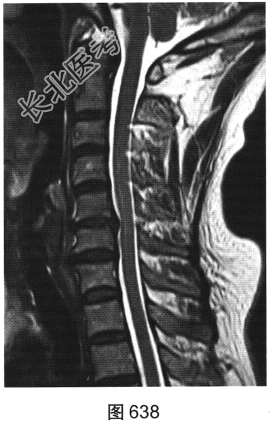

- 多项选择题3.[提示]患者保守治疗2个月后复查MRI,见图638~图642。复查的MRI图像与前次比较, 有哪些影像学变化( )

A、病变明显变小

B、颈前软组织强化

C、增强后未见强化

D、增强后可见小片状强化

E、C

间盘信号有变化F、硬膜囊及颈髓受压缓解

关注下方微信公众号,搜题查看答案